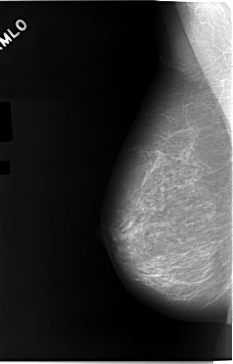

C_0046_1.LEFT_MLO

LEFT_MLO LINES 5824 PIXELS_PER_LINE 3456 BITS_PER_PIXEL 12 RESOLUTION 50 OVERLAY